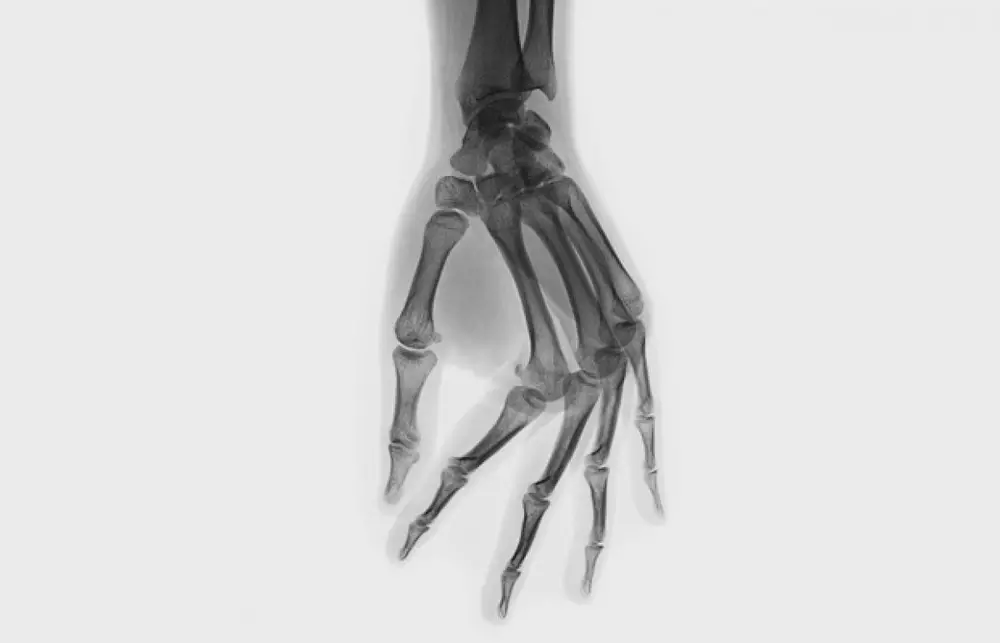

Существуют две гипотезы, объясняющие хруст в суставах. Первая предполагает, что независимо от излюбленной техники - дергаете ли вы палец или выкручиваете шею - происходит одно и то же: суставная капсула растягивается, ее объем увеличивается, а давление, наоборот, падает. Из-за этого суставная жидкость растекается, и в ней образуются пузырьки газа. Эти пузырьки лопаются с характерным звуком. Спустя 10-20 минут газы снова растворяются в жидкости - тогда можно хрустнуть еще раз. Согласно второй гипотезе, хруст возникает при движении из-за быстро натягивающихся связок и сухожилий. Когда капсула, сухожилия и связки растягиваются, сустав делается подвижнее, и человек чувствует комфорт. Ну а кому-то просто нравится звук.